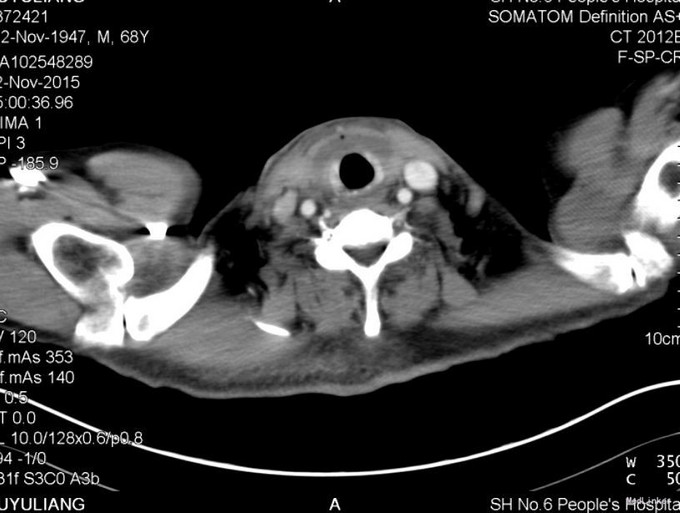

患者男,67岁。发现甲状腺结节4年余,近1个月增大明显,无声音嘶哑,无吞咽困难。

查体:颈软,气管居中,无颈静脉怒张,无触及明显淋巴结肿大,右侧甲状腺可触及肿块,质硬,无压痛,边界清,活动度可,随吞咽上下移动,未闻及血管杂音。 辅助检查: 2015-11-2 门诊化验检验报告:白细胞 6.1 *10^9/L ,红细胞 5.47 X10^12/L ,血红蛋白 168 g/L ,血小板 121 X10^9/L ↓,中性细胞百分比 62.3 % 。生化检验报告:白蛋白 47 g/L ,总胆红素 14.3 μmol/L ,血清钾 3.9 mmol/L ,血清钠 144 mmol/L ,血清氯 104 mmol/L 。生化检验报告:血糖 12.08 mmol/L ↑。放免DPC(同位素)检验报告:游离T3 5.07 pmol/L ,游离T4 15.92 pmol/L ,促甲状腺激素 0.98 mIU/l 。钙(干式) 2.06 mmol/L ↓。放免DPC(同位素)检验报告:甲状旁腺激素 45.65 pg/ml 。甲状腺超声:右侧见甲状腺部分钙化灶,提示右甲状腺乳头状癌可能,右侧四区多枚淋巴结肿大,左侧无肿大淋巴结。普放报告检查报告:两肺野纹理增多。喉镜报告检查报告:喉镜:咽喉炎 声带白斑(左)。

考虑甲状腺恶性肿瘤,患者入院后予以完善相关检查,排除手术禁忌,于2015.11.5日全麻下行双侧甲状腺全切除+喉返神经探查+右侧颈部淋巴结清扫术,手术顺利,术中出血少,术后以对症支持治疗,现患者一般情况可,予以出院。

术后病理:2015-11-9 病理检查报告:右中央区淋巴结 (右中央区淋巴结):淋巴结(5/6枚)见癌转移。病理检查报告:喉返神经后淋巴结 (喉返神经后淋巴结):淋巴结(4/4枚)见癌转移;另见癌结节一枚。备注:本例与病理号2015-35515、2015-35518、2015-35520为同一病例。病理检查报告:左甲状腺:增生甲状腺组织。大体检查:甲状腺组织,大小5*3*1cm,切面未见明显结节。2015-11-10 病理检查报告:右侧甲状腺 (右侧甲状腺)甲状腺髓样癌,肿瘤呈多灶性生长。免疫酶标记结果:肿瘤细胞CK19部分+、TPO-、G-3-、HBME-1-、PTH-、Calcitonin+、SYN+、CHG+、TG-、TTF-1+、CK+、Ki-67(1%+)大体检查:甲状腺组织6*2.5*2.5cm,切面见灰白结节2枚,大者直径1cm,小者0.5*0.2*0.2cm,结节周围见散在灰白小点。 术后复查 CT报告检查报告:甲状腺癌术后,双侧颈部积气、纵隔气肿,随访。